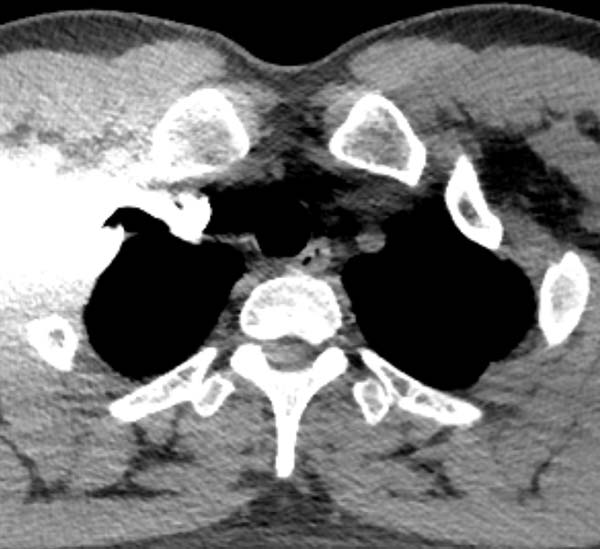

2) 左上肢留置针穿刺高速团注对比剂时,不但行程远、还受主动脉弓压迫导致进入右心房的时间延长,同等体重患者需增加注射压力和药量。

进入肺循环的造影剂总量不足

导致监测层CT值曲线迟迟达不到触发值